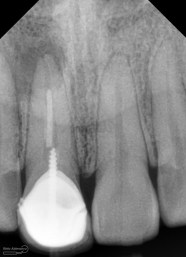

dan saya lebih terkejut ketika melihat foto ronsennya

ini dia ronsen nya….

dari ronsen ini terlihat saluran akar belum diisi dengan baik, kemudian juga ada pasak ulir yang tidak ada retensi sama sekali… di ujung apeks ada gambaran radiolusensi…